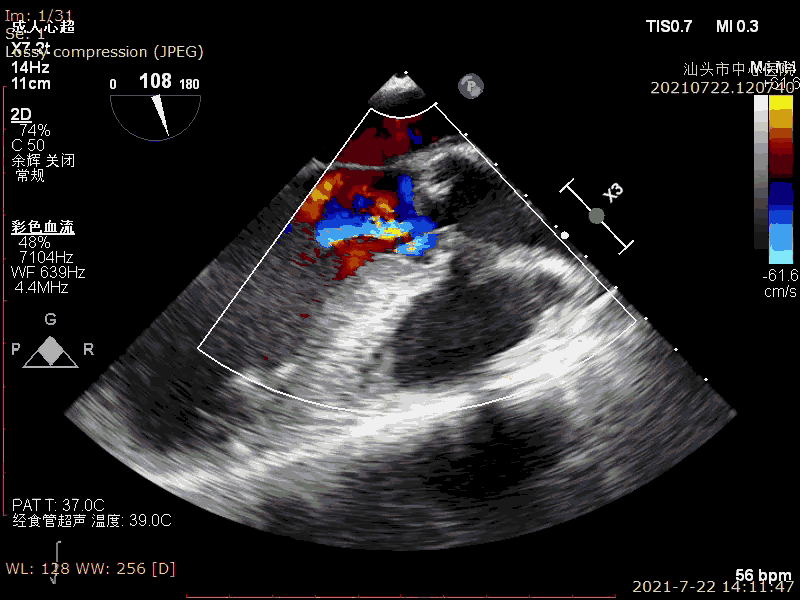

术前超声

术后超声